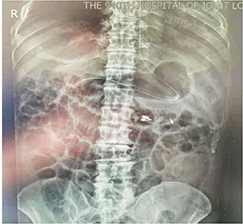

诊疗过程:入院后针对患者间断性便血,给予抑酸、止血、输血、补液、支持等治疗后便血未见明显缓解。入院后第3天急诊行SBE检查示:十二指肠及空肠近段肠腔内见大量鲜红色血液,进镜至空肠距幽门约1.5 m未发现出血灶(图1A)。退镜,冲洗、吸引观察,于空肠上段发现一大小为0.5 cm×0.5 cm的浅表凹陷性溃疡,缺损中间有血管走行,表面可见凝血块附着(图1B),且有搏动性出血,无明显炎性改变,考虑为Dieulafoy溃疡(图1C)。注射硬化剂止血(图1D)并联合钛夹止血(图1E、F),确认出血停止后结束治疗。术后继续辅以输注悬浮红细胞,并进行抑酸、保护胃黏膜、调节肠道菌群等综合治疗。术后腹部X线平片示钛夹位于空肠上段(图2),腹部增强CT未见明显异常。患者的病情逐渐平稳要求出院回家休养。1个月后复查SBE,Dieulafoy溃疡完全愈合,两枚钛夹残留(图3),继续随访7个月未再出现便血症状。

注:钛夹位于空肠上段